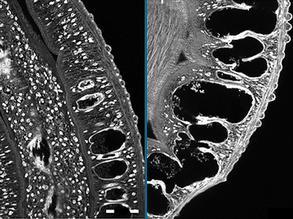

Schwann's Way